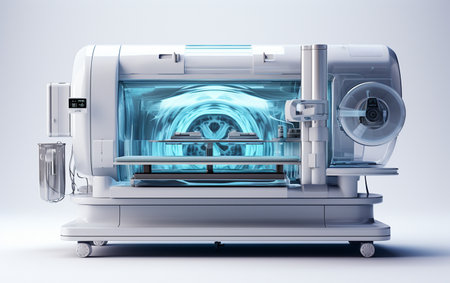

medical scanner, with close-up of intricate and complex circuitry, created with generative ai

CT scanner machine in modern medical laboratory. 3d rendering toned image

Radiographic Machine White Setting

CT scanner, medical background.

Advanced MRI,CT Scan Machine: Medical Diagnosis in Hospital Lab. Generative ai. High quality illustration

Mri or Computed tomography scan medical diagnosis machine